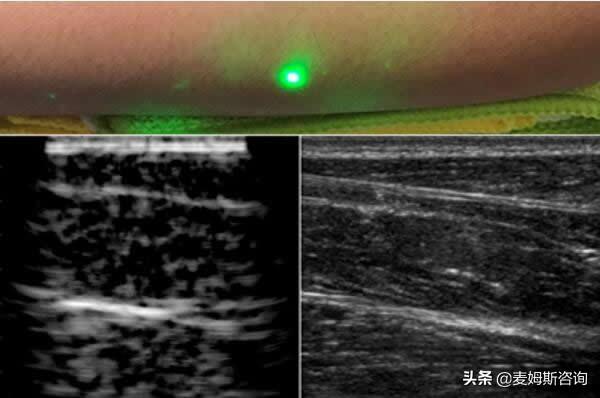

而在日常的健康监测中,超声成像同样扮演着不可或缺的角色。当人们因为身体的不适走进医院,心中难免带着忐忑与担忧,此时超声检查就像一位细心的 “侦察兵”,悄无声息地穿梭在身体的各个器官之间,寻找着可能存在的异常。它不需要借助复杂的侵入性操作,也不会给身体带来额外的负担,只需要通过探头的轻轻滑动,就能清晰地呈现出肝脏、肾脏、甲状腺等器官的形态与结构。医生通过这些影像,能够及时发现潜在的问题,比如微小的结节、异常的积液,或是器官功能的细微变化。对于患者而言,这样的检查不仅是对健康状况的准确评估,更是一颗定心丸,让他们能够在了解自身情况后,更从容地面对后续的治疗与调理。

在急诊的紧张场景里,超声成像更是展现出了惊人的速度与精准。当意外发生,患者生命垂危的时刻,每一分每一秒都至关重要。此时,便携式超声仪可以迅速抵达患者身边,在最短的时间内完成对心脏、肺部、腹部等关键部位的检查,帮助医生快速判断患者是否存在内出血、气胸、心包积液等危及生命的情况。没有繁琐的准备流程,也没有漫长的等待时间,超声影像如同及时雨般,为医生的紧急决策提供了有力的依据,为患者的生命抢救争取了宝贵的时间。在那些与死神赛跑的瞬间,超声成像用无声的速度与精准,为生命筑起了一道坚实的防线。